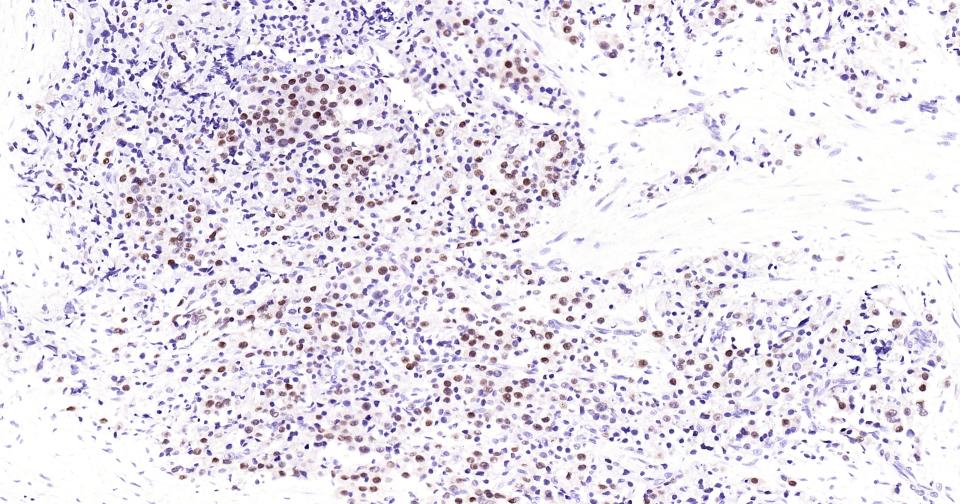

Paraformaldehyde-fixed, paraffin embedded Human Prostate Tumor; Antigen retrieval by boiling in sodium citrate buffer (pH6.0) for 15 min; Antibody incubation with Androgen receptor Monoclonal Antibody, Unconjugated(bsm-61204R) at 1:200 overnight at 4°C, followed by conjugation to the SP Kit (Rabbit, SP-0023)and DAB (C-0010) staining.